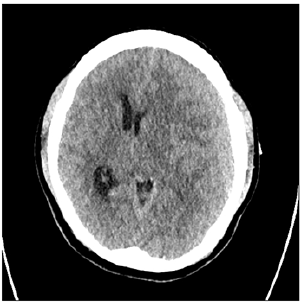

Figure 1: 84-year-old male patient presented with headache and right-side weakness. Brain CT showed a CSDH with midline shift.

The age range was from 20 to 90 years with mean age of 66.5 years (Table 1). There were 122 (70.5%) males and 51 (29.5%) females. Clinically, headache was found in 83 (47.9%), hemiparesis in 141 (81.5%). There were 85 (49.1%) of patients who had the right side, 65 (37.6%) in the left side, and 23 (13.3%) in bilateral CSDH (Table 1). Radiologic follow-up showed removal of the CSDH in all cases with minimum residual in the early postoperative period and complete resolution at late follow-up. All patients were showed good clinical outcomes comparing preoperative period. Mean post-op hospital stay day was 4.5 days (range 3-8). 19 patients (10.7%) show residual CSDH cannot be drained but follow up study shows complete resolution of the CSDH. No patient required revision and no acute hematoma formation. Illustrative case (residual hematoma) A 84-year-old male patient presented with headache and right-side weakness. Brain CT showed a CSDH with midline shift. We performed burr hole drainage under local anesthesia. Postoperative patient response was good, and the patient’s symptoms was gone. However, f/up CT showed residual CSDH [9-14]. The patient symptom was good, so we wait and f/up the patient. The patient symptom was consistently good, so we did not perform further treatment and after 6months f/up CT showed total resolution of residual CSDH (Figures 1-3).